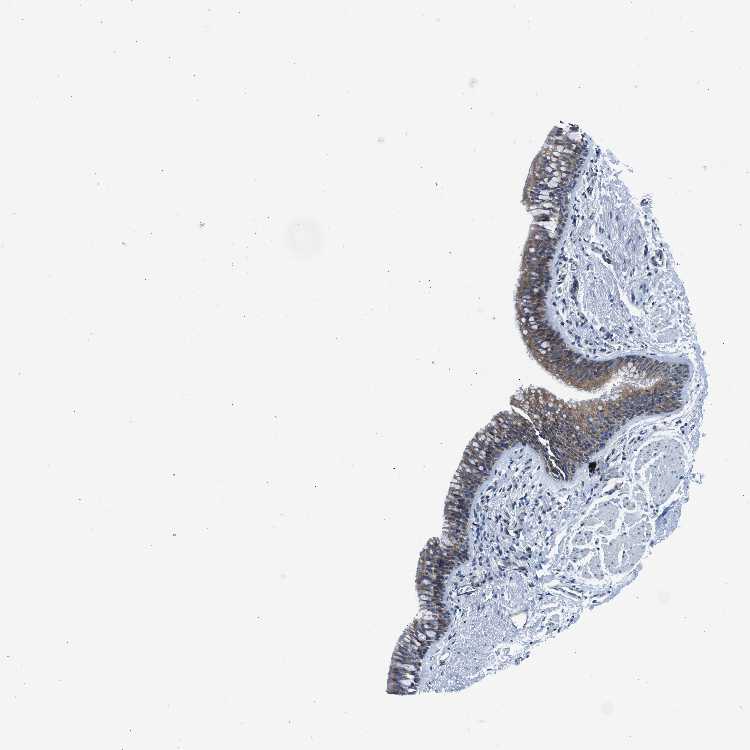

ADIPOSE TISSUE - Antibody stainingi

Antibody staining in the annotated cell types in the current human tissue is reported as not detected, low, medium, or high, based on conventional immunohistochemistry profiling in selected tissues. This score is based on the combination of the staining intensity and fraction of stained cells.

Each image is clickable and will lead to virtual microscopy that enables deeper exploration of all samples and also displays staining intensity scores, fraction scores and subcellular localization as well as patient and tissue information for each sample.

Antibody HPA016867Antibody HPA018271

Adipocytes LowMedium